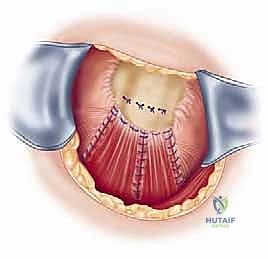

ثم يتم زرع خطاطيف جراحية (Suture Anchors) متطورة (مصنوعة من التيتانيوم أو مواد قابلة للامتصاص) داخل العظم.

هذه الخطاطيف متصلة بخيوط جراحية فائقة القوة. يقوم الدكتور هطيف بتمرير هذه الخيوط عبر الوتر الممزق باستخدام تقنيات خياطة معقدة (مثل صف مزدوج Double Row) لضمان توزيع الضغط وتوفير تثبيت ميكانيكي صلب.

يتم ربط العقد الجراحية بإحكام، ويتم اختبار حركة الكتف على طاولة العمليات للتأكد من متانة الإصلاح وقدرة الوتر على تحمل الشد.